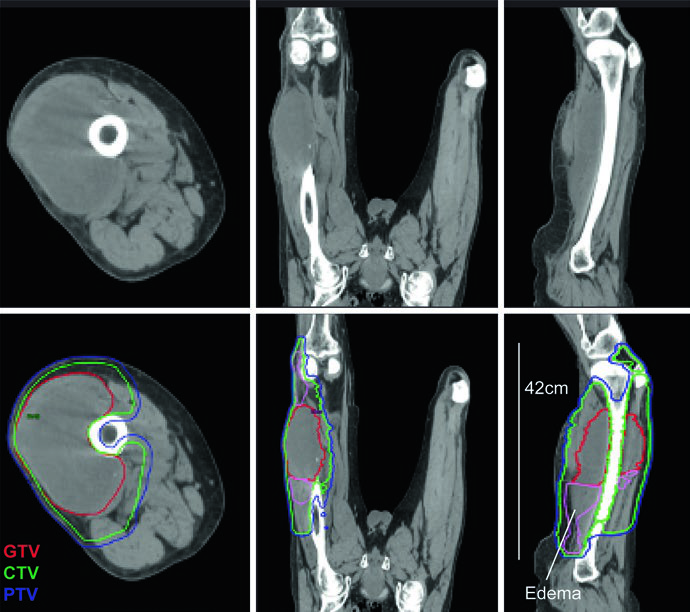

El edema peritumoral en sarcomas de extremidades puede alcanzar extensiones notables. Un caso ilustrativo del texto describe un mixofibrosarcoma grado 2 de muslo lateral con edema peritumoral masivo extendiéndose superior e inferiormente, resultando en un PTV de 42 cm — superando la capacidad máxima de campo para técnicas de isocentro único en la mayoría de los aceleradores lineales.

La solución empleada fue una técnica IMRT de doble isocentro, con los isocentros posicionados estratégicamente cerca del centro de cada subvolumen adyacente y cooptimizados para garantizar cobertura uniforme del PTV en la zona de unión. Esta situación refuerza la importancia de mapear completamente el edema en la RM T2 antes de la simulación: subestimar la extensión del edema compromete la cobertura terapéutica. La RM sagital resulta particularmente valiosa para delimitar la extensión craneocaudal.

Un detalle crítico: el CTV queda limitado por el hueso a lo largo de todo el volumen blanco. El SPB respeta barreras como hueso cortical y membranas interóseas, de modo que no es necesario expandir el volumen dentro del hueso. Este principio de preservación tisular reduce significativamente la toxicidad tardía. Para consideraciones adicionales en pacientes más jóvenes, consulte nuestro artículo dedicado al sarcoma pediátrico.